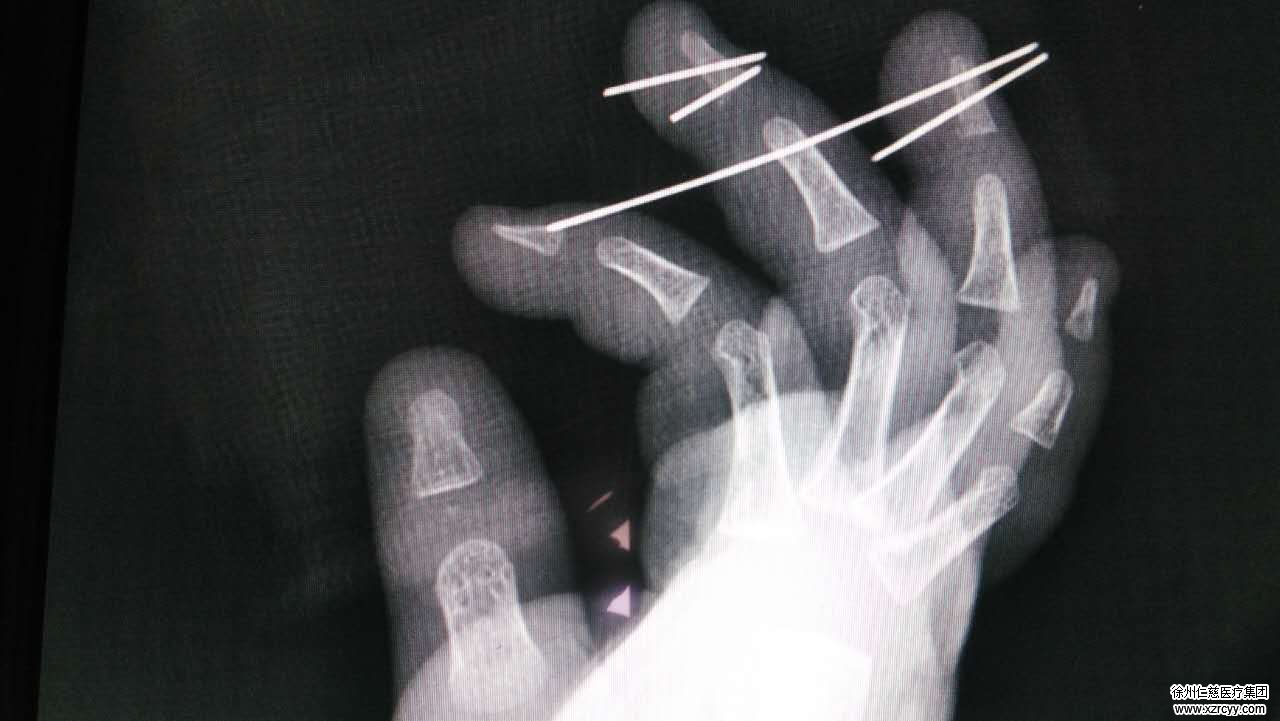

李明说,sararz手外专家团队给小宝做了右中环指清创、右中环指骨折复位内固定,血管神经撕脱皮肤修复术,孩子年龄尚小,所以医生采取了全麻的方式,术后配合后期的康复训练,不出意外的话,以后孩子的手是可以恢复到正常的。